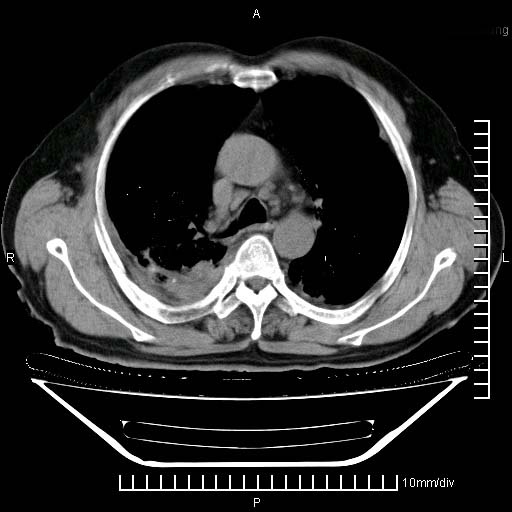

标题: CT24043:胸部增强:男性,60岁

既往肺结核,近10几天,咳嗽,咳痰,右侧胸痛,疼痛较明显,右上肺斑块考虑结核灶胸膜粘连,增强,可惜动脉期没有定好,未见强化,可延迟4分后又见较明显强化,中心见低密度影,如果说结核是边缘强化,可这个灶强化的面积挺大的,让人很挠头。

1)两肺继发性肺结核。2)右侧胸膜增厚+少量胸腔积液。